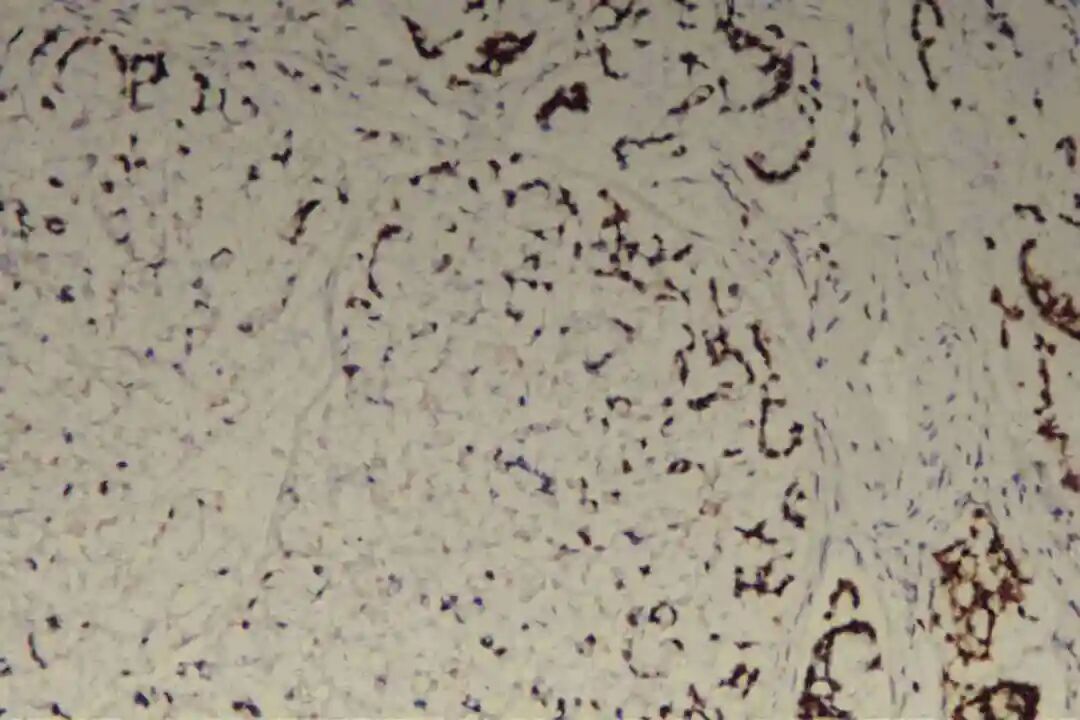

免疫组化:Her-2(0),P53(突变表型),CK20(+),CDX-2(+),SATB-2(-),Syn(+),INI-1(SMARCB1)(+),BRG1(SMARCA4)(+),Ki67(90%+),INSM1(灶+),CgA(-);

1.Syn(突触素):是神经内分泌细胞的特异性标志物,阳性提示肿瘤存在神经内分泌分化,即肿瘤细胞同时具备腺上皮分泌黏液与神经内分泌细胞分泌肽类激素的双重特征。

2. 免疫组化确认:Syn阳性是核心标志,常联合CgA(嗜铬粒蛋白A)、NSE(神经元特异性烯醇化酶)等提升神经内分泌分化检出率,同时需检测原发部位特异性标志物(如乳腺ER/PR/HER2、肺CK7/TTF - 1、胃肠道CK20/CDX - 2)以明确来源与分型。